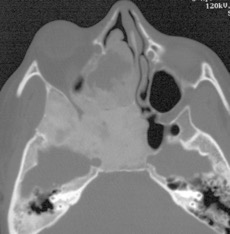

il n’y a le plus souvent pas de compression des structures nerveuses, en particulier les nerfs optiques qui sont souvent englobés dans l’os malformé sont en général préservés ; c’est seulement dans les cas de dysplasie avec remaniements kystiques et/ou hémorragique (cf. ci-contre) que la compression du nerf optique peut nécessiter un geste décompressif en urgence.

l’ostéopétrose

il s’agit également d’une maladie du remaniement de la structure osseuse, la voûte est très épaissie avec fermeture des sutures, qui peut rendre nécessaire une cranioplastie d’agrandissement crânien avec fraisage de la voûte cf. ci-dessous. à la différence de la dysplasie fibreuse, l’ostéopétrose entraîne une compression des canaux optiques qui peut nécessiter une décompression chirurgicale.